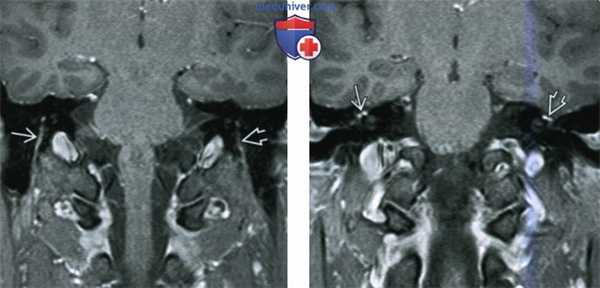

(Слева) МРТ, постконтрастное Т1 -ВИ, режим подавления сигнала от жира, аксиальный срез: определяются классические признаки паралича Белла: признак «хохолка» в области дна внутреннего слухового прохода, контрастирование лабиринтного и барабанного сегментов лицевого нерва.

(Справа) МРТ, постконтрастное Т1-ВИ, режим подавления сигнала от жира, аксиальный срез: у этого же пациента вновь определяется признак «хохолка» в области дна ВСП и контрастирование барабанного сегмента лицевого нерва. Следует помнить, что коленчатый ганглий и заднее колено/верхний сосцевидный сегмент лицевого нерва могут контрастироваться в норме. (Слева) МРТ, постконтрастное Т1-ВИ, режим подавления сигнала от жира, аксиальный срез: у этого же пациента в области шилососцевидного отверстия определяется контрастирование и легкое увеличение лицевого нерва. Набухание лицевого нерва возможно вне канала лицевого нерва височной кости.

(Справа) МРТ, постконтрастное Т1-ВИ, режим подавления сигнала от жира, корональный срез: у этого же пациента, страдающего параличом Белла, отмечается выраженное контрастирование сосцевидного, шилососцевидного и экстракраниального отдела лицевого нерва.